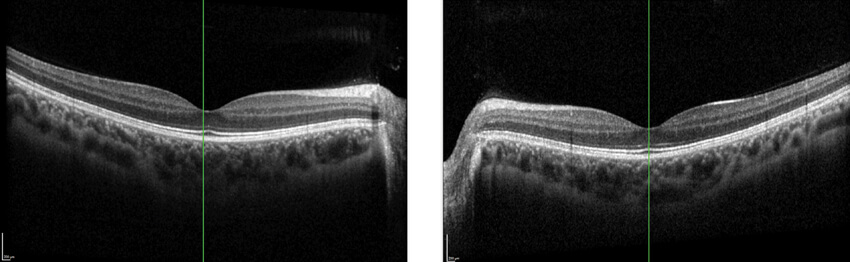

His best corrected visual acuity was OD 6/9 and OS 6/6, with no improvement on pinhole examination in either eye. His intraocular pressure was OD 17mmHg and OS 14mmHg. Colour vision was normal on Ishihara testing (15/15). Optical coherence tomography (OCT) was done and revealed no abnormalities in the optic disc or macular region (Figure 1).

Figure 1: Optical coherence tomography scans of the right eye (OD) and the left eye (OS).